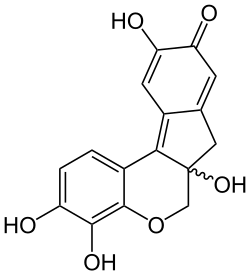

| Strukturformel | ||||||||||||||||||||||

In seiner reinen Form ist Hämatoxylin farblos bis beige. Durch Oxidation mittels Luftsauerstoff (langsam) oder einem geeigneten Oxidationsmittel (z. B. Natriumiodat, Kaliumpermanganat, Wasserstoffperoxid oder Iod) entsteht in wässriger oder alkoholischer Lösung aus Hämatoxylin das ockerbraun gefärbte Hämatein. Diesen Vorgang nennt man auch (natürliche bzw. künstliche) „Reifung“. Hämatein ist ein leicht saurer Farbstoff. Die gewünschte färbende Wirkung wird erst durch den Zusatz mehrwertiger Metall-Kationen als Beize erreicht. In Gegenwart mehrwertiger Kationen, wie z. B. Eisen (Fe3+) und Aluminium (Al3+) bilden sich Farbstoffkomplexe durch Chelatbildung in der Stöchiometrie 1:1. Komplexe aus Hämatein und Alaunen werden dabei als Hämalaune bezeichnet. Hämalaune zeigen die typische dunkelblau-violette Farbe und werden auch als Hämatoxylinlack (eigentlich Hämateinlack) bezeichnet.

Durch Variation des pH-Wertes kann eine Selektivität für verschiedene Strukturen erreicht werden. Während bei einem pH-Wert von > 4,5 zahlreiche Zellstrukturen gefärbt werden, dominiert bei einem pH-Wert von 2–3 die Anfärbung von Zellkernen. Brasilin fehlt im Vergleich zu dem Farbstoff Hämatoxylin eine Hydroxygruppe.